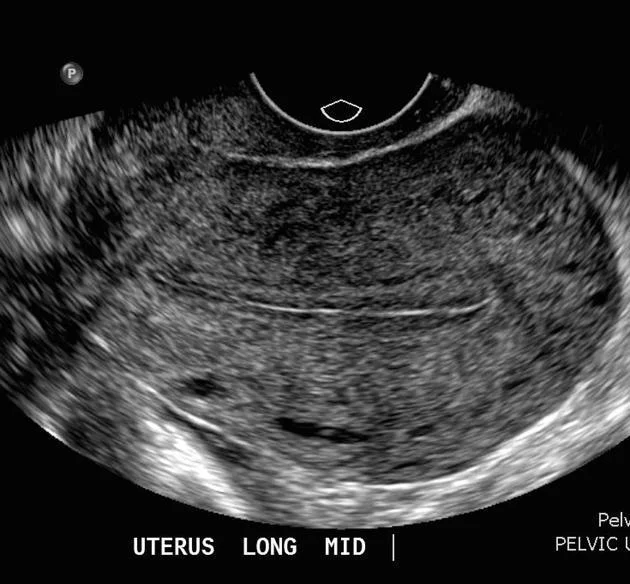

Complete miscarriage

- Clinical feature:

- Expulsion of all products of conception.

- Cessation of bleeding and abdominal pain.

- on examination:

- P.V.: closed cervix.

- Investigations:

- US: empty uterus.

- Treatment:

- Supportive.